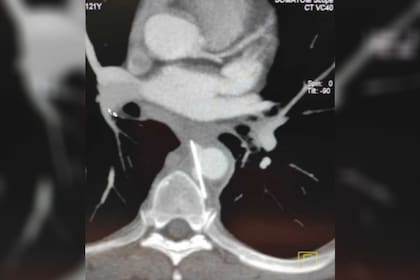

“Hoy operamos al paciente que ingresó hace una semana desde el Pirovano. Ahora está siendo monitoreado para ver cómo evoluciona”, expresó Adrián Desiderio, quien es Jefe de Cirugía del ya mencionado Hospital Durand, en diálogo con la agencia Noticias Argentinas. “La aguja era de tres centímetros y medio, perforó el esófago y quedó alojada entre la aorta y la vértebra”, completó.

Fue gracias a una tomografía computada que el objeto pudo ser identificado y, mediante la aplicación de un stent, comenzó el tratamiento para finalmente retirarla. “Tomamos la determinación de sacarla porque puede migrar y provocar daños mayores en el cuerpo”, precisó el médico. Si bien ahora comenzará un post operatorio que llevará varios meses, los médicos expresaron que con el tiempo logrará volver a una vida normal.